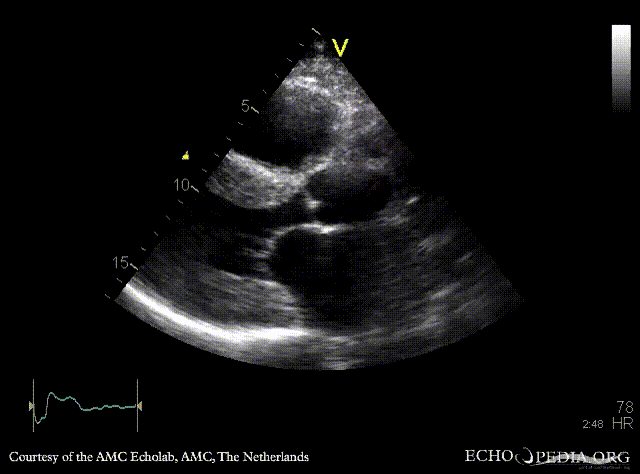

Amyloidosis

A4CH: concentric left and right ventricle hypertrophy with reduced systolic function, biatrial enlargement Subcostal view: concentric left and right ventricle hypertrophy